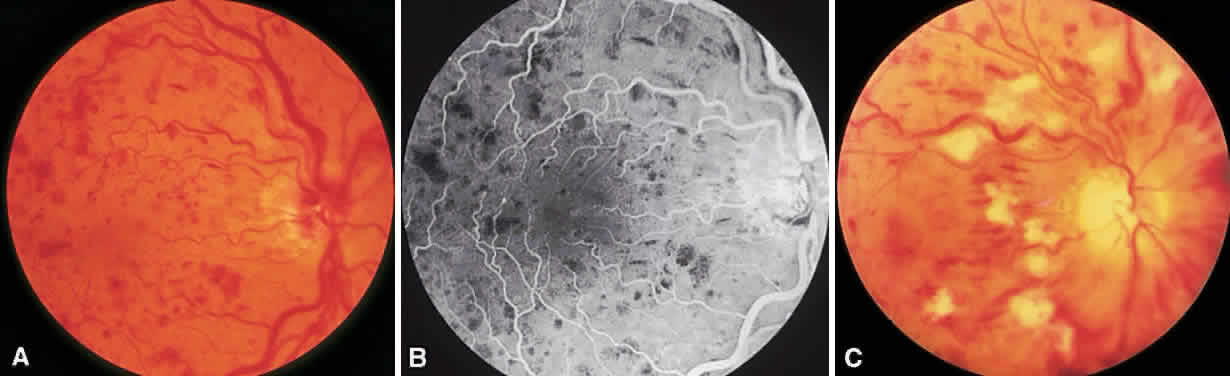

CRVOs are usually described as “ischemic” or “nonischemic” based on clinical examination and FA findings (Fig. 6). Roughly 75% to 80% of CRVOs are nonischemic. However, up to 34% of these will progress to the ischemic type usually within 1 year.46,47,50,51 An eye with a nonischemic CRVO typically has minimal capillary nonperfusion on FA, relatively few intraretinal hemorrhages, and a better visual prognosis than the ischemic variety. Ischemic CRVOs, conversely, have widespread capillary nonperfusion and are associated with a worse visual prognosis with increased risk of rubeosis iridis and neovascular glaucoma.52

Fig. 6. Nonischemic (A and B) and ischemic (C) central retinal vein occlusion.

The Central Vein Occlusion Study (CVOS) was a prospective, randomized, multicenter clinical trial designed to evaluate the role of PRP in promoting regression of anterior segment neovascularization resulting from ischemic CRVO, to determine the efficacy of macular grid laser photocoagulation for treating CRVO-related macular edema associated with visual acuity of 20/50 or worse, and to define the natural history of CRVO.53

The CVOS demonstrated that, although prophylactic PRP does decrease the risk of developing anterior segment neovascularization, prompt regression of neovascularization was more likely in eyes that had not received prior laser photocoagulation.54 Therefore, the study recommends observing ischemic CRVOs closely and treating with PRP at the first sign of iris or angle neovascularization rather than treating prophylactically. PRP may be warranted in the setting of acute ischemic CRVO if there is a high likelihood of poor patient compliance with follow-up. Unlike the BVOS, the CVOS did not demonstrate any benefit to laser photocoagulation for macular edema.55 Although laser therapy did decrease the amount of leakage on FA, there was no difference in visual acuity between treated and untreated eyes at any point in follow-up.